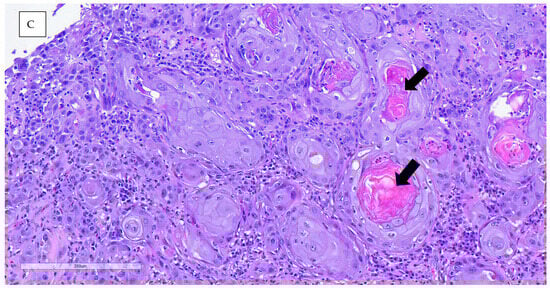

An incisional biopsy was performed in order to obtain further information. Anesthesia was conducted via inhalation of isoflurane. The biopsy was processed routinely with paraffin-embedded tissue and hematoxylin–eosin (H&E) stain for histopathological study. Histopathological analysis revealed neoplastic proliferation, characterized by nonencapsulated, poorly demarcated, and infiltrative growth, which effaces and replaces the epidermis and dermis, reaching the surgical margins. The neoplasm was arranged in nests of multiple layers with squamous differentiation (keratin pearls), surrounded by desmoplastic mature connective tissue. The neoplastic cells were polygonal, with abundant eosinophilic cytoplasm and partially defined cellular borders. One or more nuclei were present, round to oval in shape, with stippled chromatin. The anisocytosis and anisokaryosis rates were high, and the mitotic count was moderate. Other microscopic findings included severe epidermal ulceration replaced by serocellular crusts, peripheral epidermal hyperplasia with hyperkeratotic orthokeratosis, and severe interstitial inflammatory infiltrate mainly composed of heterophils, lymphocytes, and plasma cells. The definitive diagnosis for both lesions was invasive squamous cell carcinoma, accompanied by ulcerative and heterophilic dermatitis. The nature of the dermatitis was determined to be subacute to chronic, with the presence of bacterial contamination (Figure 5).

Figure 5.

(A) The microscopic images showed orthokeratotic and epithelial neoplastic proliferation, not encapsulated or well delimited and infiltrative. Intense hyperkeratosis is observed in the non-ulcerated epidermis. (B,C) Neoplastic cells growing, forming nests of multiple layers with scaly differentiation, with some pearls of keratin observed. They are surrounded by an abundant amount of mature fibrous tissue interstitial (intense fibrous desmoplasia). The neoplastic cells are polygonal, with abundant eosinophilic cytoplasm and well-defined cytoplasmic borders.